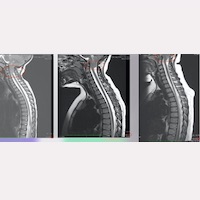

Fig.1 Ressonâncias Magnéticas de uma paciente durante o seu curso pós-operatório a longo prazo

, no qual, 6 anos após a cirurgia do FS®, quase não é possível detectar o deslocamento das amígdalas cerebelosas para baixo que,

anteriormente, era muito acentuado.

Entre os casos analisados pelo nosso Instituto, esta ascensão foi observada, em alguns deles, entre 1 e 2 anos após a cirurgia, enquanto que, em outros, isto ocorreu ao longo dos primeiros 5-10 anos pós-operatórios (Fig. 1).